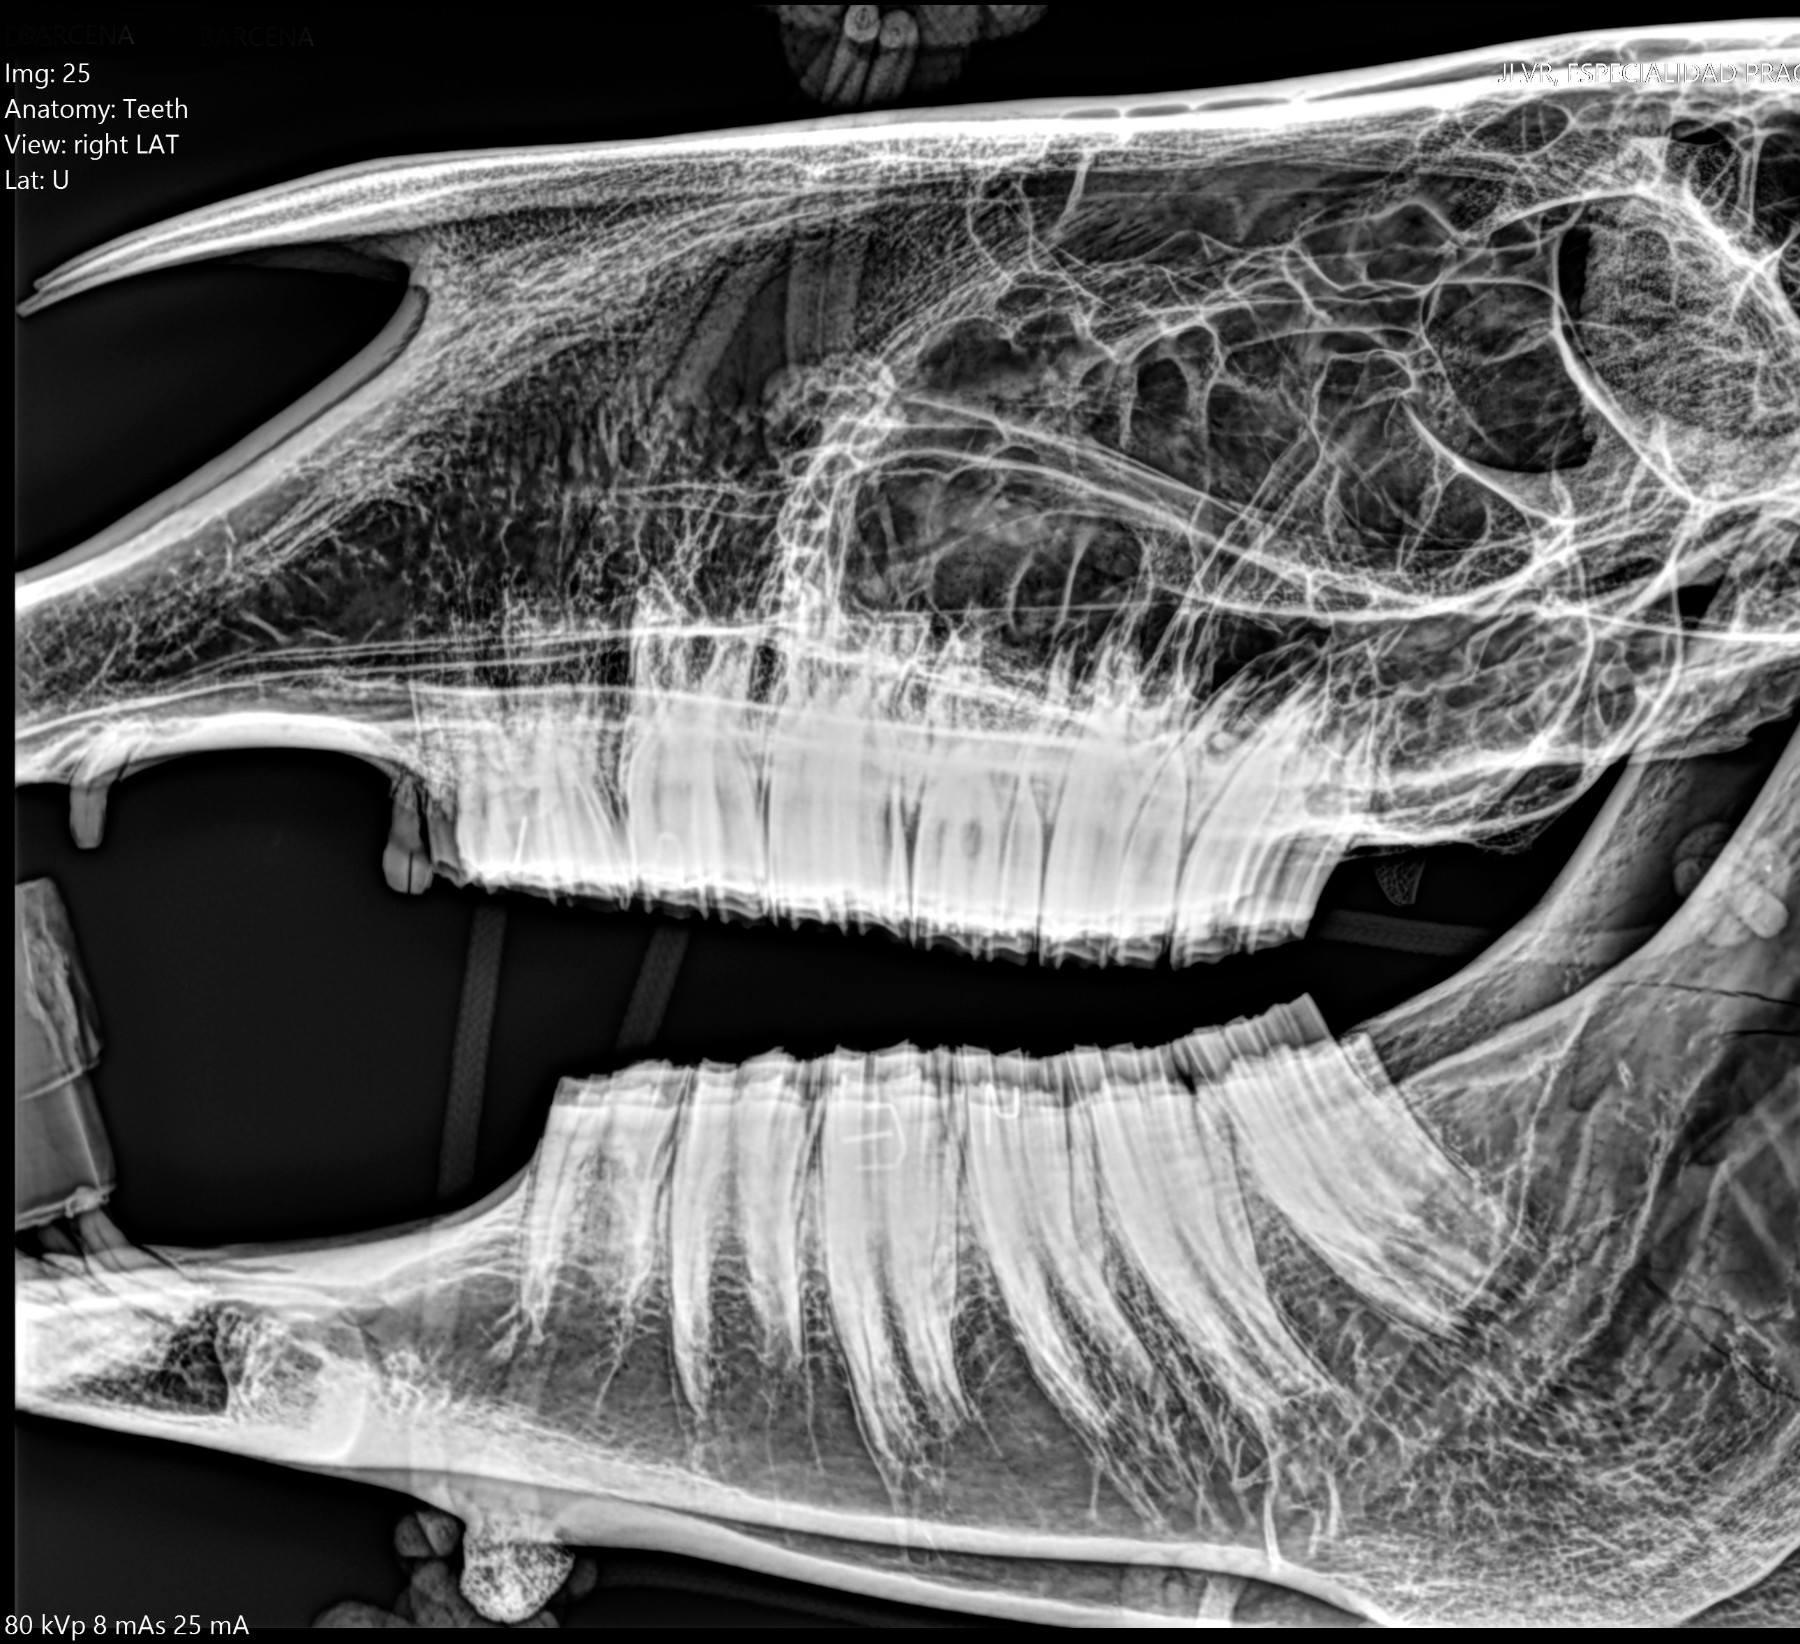

Radiología Digital como Herramienta Complementaria en el Dictamen de Bienes Muebles

Desde el descubrimiento de los rayos “X” y las placas radiográficas por Wilhelm Conrad Roentgen y su posterior difusión a través de la Asociación Físico médica de Wurzburg el 28 de diciembre de 1895, que fue la primera asociación que habló de los nuevos rayos que podían penetrar el cuerpo y fotografiar los huesos, ha habido muchos cambios tanto en la forma de obtener, procesar e incluso en la forma de visualizar, manejar y almacenar las placas radiográficas.